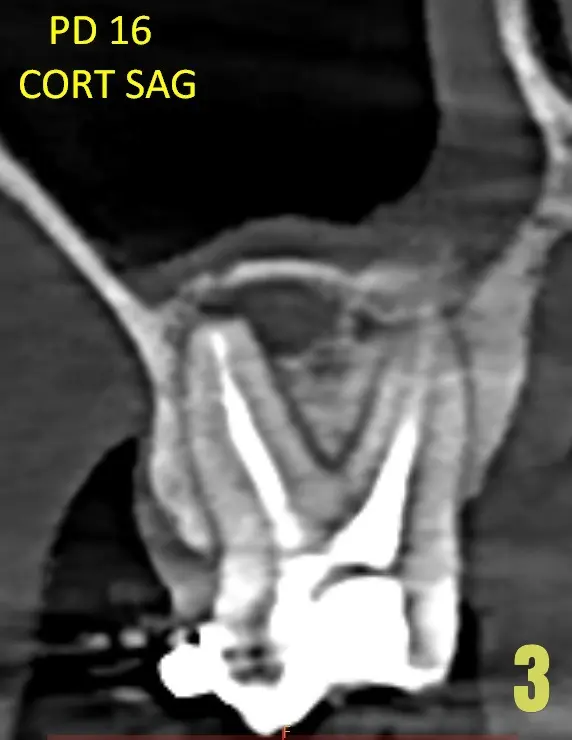

Pieza dental 16 presenta tratamiento de conducto, donde se logra observar lesión periapical.(Imagen 03)